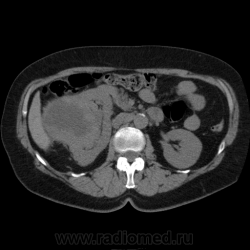

Солитарное кистовидное образование правой почки с неравномерно утолщенными стенками, у узлами в капсуле, накапливающими контраст. Фасция Гарота справа тяжистая. По классификации - киста 4-й категории, крайне велика возможность малигнезации. Может, показалось вовлечение парааортальных лимфоузлов?

В 1986 г. M.A. Bosniak создал “рабочую” классификацию кистовидных образований почек, которая позволяет предположить доброкачественность или злокачественность кистозных образований при распределении их по радиологическим критериям на 4 основные категории. Образования I и II категорий являются заведомо доброкачественными и поэтому нуждаются в динамическом наблюдении или, по показаниям, в лечебной пункции со склеротерапией под контролем УЗИ или КТ. Образования III категории могут быть как доброкачественными, так и злокачественными, а образования IV категории – кистозные почечноклеточные раки.

Третья категория – более сложные кистовидные образования, которые демонстрируют какие-либо радиологические признаки злокачественности. Некоторые из этих образований оказываются доброкачественными (например, сложные кисты, мультилокулярная кистозная нефрома, геморрагические кисты), другие злокачественными (почечные кистозно-клеточные карциномы). Одним из критериев, которые заставляютотнести кистовидное образование почки к III категории, является повышение плотности ее стенки. При КТ у кистовидного образования выявляется плотная (вплоть до обызвествления) стенка по всему периметру кисты, хотя образование может сохранять некоторые признаки простой кисты почки. Следующим критерием является характер отложения кальцинатов. Если при КТ в образовании определяется большое количество кальцинатов, расположенных глыбками (как на периферии образования, так и в центре), если из-за этого стенки и перегородки становятся утолщенными, неправильной формы, то данное образование следует отнести к III категории. Наличие множественных перегородок толщиной более 1 мм, видимых утолщений в месте прикрепления перегородок к стенкам кисты позволяет также отнести данное образование к третьей категории. Большое количество тонких перегородок в образовании определяет его как сложную кисту. Такие образования крайне сложно дифференцировать как доброкачественные или злокачественные, но они чаще по КТ-картине выглядят как злокачественные. При КТ определяется негомогенное многокамерное образование округлой или неправильной округлой формы, возможно с капсулой. Плотность образования неоднородная, пониженная относительно паренхимы, в полости образования видно большое количество перегородок.

IV категория – поражения явно злокачественные, обычно кистозные почечно-клеточные карциномы. Основными симптомами кистозной опухоли при КТ являются: неправильная форма кисты, негомогенность структуры образования с участками некроза, деформация почки, нечеткая граница между кистой и паренхимой почки, плотностные показатели могут быть выше, чем в кистах (+20…+40 Н), т.е. близкие к плотности почечной паренхимы. Капсула имеет неравномерную толщину, часто обызвествлена по периферии. Возможна визуализация дополнительных фокусов образования (кажущееся увеличение образования в размерах и изменение его конфигурации) после введения контрастного вещества. Но самым важным симптомом является увеличение плотности внутреннего содержимого после внутривенного введения контрастного вещества. Часто на серии срезов удается выявить эндофитные гребневидные фестончатые разрастания, выступающие в просвет кистозной полости. Особенно хорошо этот мягкотканый васкуляризированный компонент опухоли проявляется при внутривенном контрастировании

Всё верно, я тоже пользуюсь данной классификацией по Босняку, кистозно-солидное образование правой почки я отнёс к 4 категории, нужно отметить, что преобладает кистозный компонент, но солидный компонент довольно приличный и значительно накапливает контрастное вещество до 80-90HU, четко капсулу образования не отграничить. Ко всему этому в паренхиматозную фазу четко дифференцируются единичные парааортальные и паракавалльные л/узлы. С большей степенью вероятности в данном случае cr почки. Пациентка на следующей неделе будет госпитализирована для верификации.

Описание изменений, выявленных при микроскопическом исследовании: опухоль представлена крупными альвеолярными структурами из светлых, оптически пустых клеток с мелкими гиперхромными ядрами, опухоль частично инфильтрирует капсулу почки, полностью прорастает стенку почечной лоханки, образуя полиповидные структуры. Одиночные опухолевые эмболы в сосудах почки. Отдельно присланный узел представлен тканью почки с опухолевым узлом, строение которого соответствует выше описанной опухоли. В воротах почки патологических образований не найдено. Во всех исследованных лимфоузлах (6 шт.) метастазы опухоли с замещением всей ткани лимфоузлов.

Патоморфологическое заключение: массивный светлоклеточный почечно-клеточный рак почки с частичной инфильтрацией капсулы, прорастанием в ЧЛС, опухолевыми эмболами в сосудах, множественными метастазами в забрюшинные лимфоузлы (6 шт